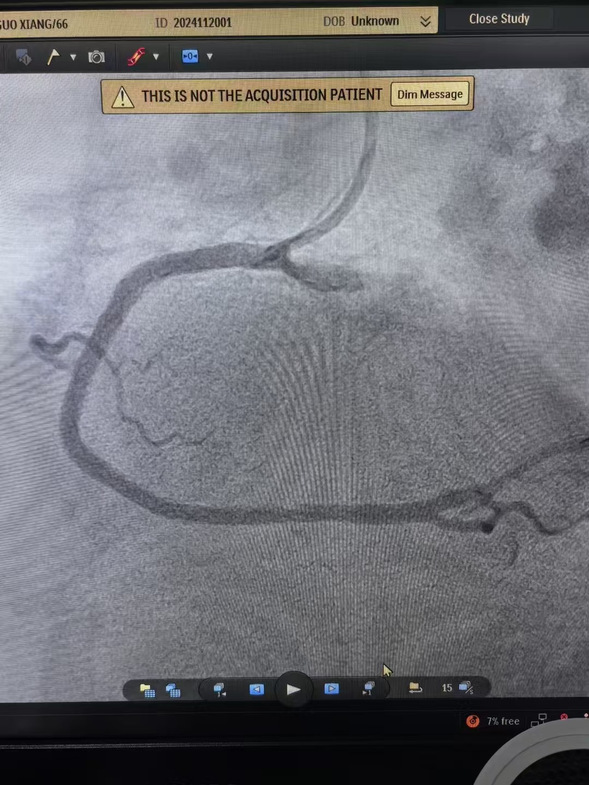

早7点,患者经120迅速到达我院大门,此时患者面色苍白、出汗明显、疼痛难止。我院医务人员立即通过绿色通道绕行急诊和病房,以最快速度将患者转移到介入手术室。在规范执行胸痛中心双绕流程基础上,心血管内四科主任沈彦祥带领医生孙智睿经临时起搏、血栓抽吸,患者胸痛症状得以缓解,状态良好。

术前、术中、术后影像